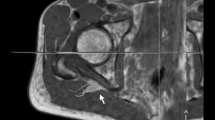

Image analysis was performed by two independent readers (M.K. and F.P. with more than 5 and 3 years of experience in neuromuscular imaging, respectively) using the DICOM-viewer OsiriX (Pixmeo Sarl, Bernex, Switzerland). Image quality was visually assessed by both readers and one participant was excluded in consensus due to severe motion artifacts, and thus the data of 27 participants were analyzed in this study. All analyses in this study refer to these 27 participants. A total of seven slices of interest were defined at mid-thigh to distal-thigh level in each scan in identical anatomical positions by F.P. and then used for independent segmentation by both readers. Segmentation of the sciatic nerve was performed in the anatomical T2-weighted image by freehand regions of interests (ROI) where nerve size and shape could be well-delineated (Fig. 2). Analysis of the sciatic nerve was restricted to the tibial portion to avoid inclusion of fat and connective tissue. The ROIs were then copied to the corresponding b0-image (b = 0) and slightly adjusted, mostly downsized, to avoid partial volume artifacts from surrounding fat tissue and to compensate possible distortion artifacts [19]. The FA, MD, AD, and RD were obtained using the OsiriX plugin DTI map with a preset noise threshold of 14. For further analysis, DTI parameters were averaged from all 7 slices.

Representative images of nerve segmentation. Segmentation of the tibial portion of the sciatic nerve was conducted independently by each reader using a free-hand ROI tool in OsiriX. ROIs were transferred onto co-registered DTI maps and slightly adjusted in the b0-image before DTI parameters were obtained. FA fractional anisotropy, MD mean diffusivity, RD radial diffusivity, AD axial diffusivity, T2w T2-weighted image